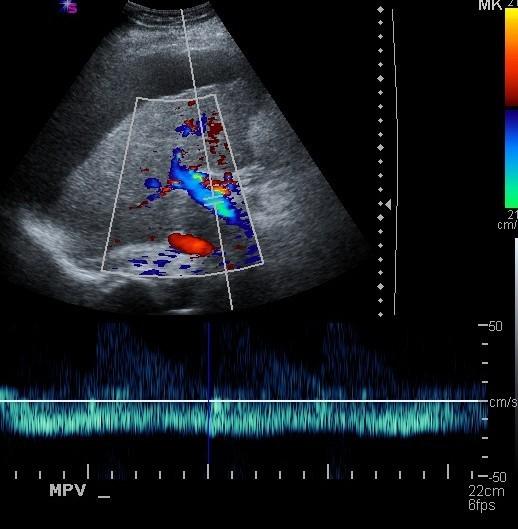

Portal Hypertension

Portal Hypertension

Portal vein Thrombosis - cavernous transformation

replacement of the normal single channel portal vein with numerous tortuous venous channels.